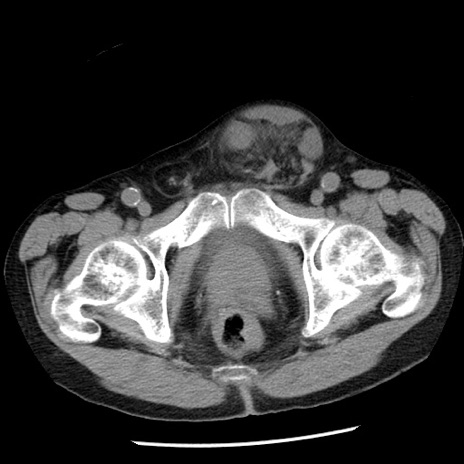

冠状断像

【症例】80歳代男性

【主訴】嘔吐

【現病歴】昨晩2回嘔吐あり、今朝になっても嘔吐あり。来院。

【既往歴】胃潰瘍

【身体所見】意識清明、BT 37.6℃、BP 166/95mmHg、HR 100bpm、SpO2 97%、腹部:平坦・軟、腸蠕動音聴取良好、圧痛なし。

【データ】WBC 21900、CRP 1.46